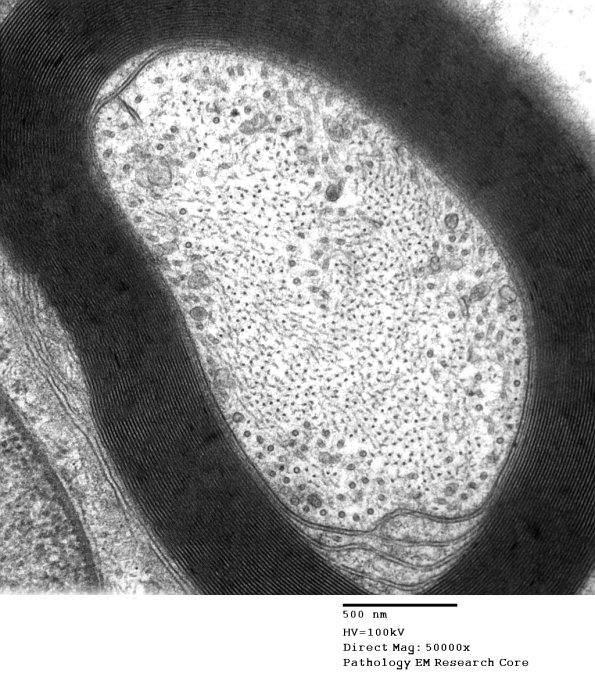

Washington University Experience | PERIPHERAL NEUROPATHY | 2 NORMAL AXON | 11A3 (Case 11 EM 003 - Copy

Higher magnification of image #11A2. (electron micrograph)